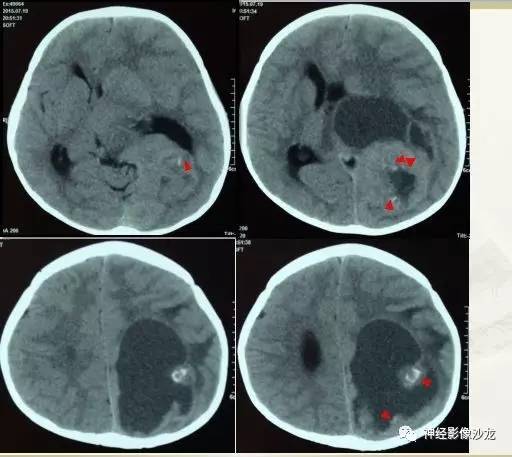

【病例】幕上脑实质内室管膜瘤1例CT及MR影像讨论

囊实性占位,有钙化,实性成分明显强化

钙化可能是个突破点

其内有钙化,DWI高信号

没出血,是钙化吧

CT是钙化

感觉有钙化,而且太大了,恶性水肿应该症状更明显了

水肿不够,钙化交成熟

室管膜瘤

儿童,侧脑室三角区旁、囊变、钙化、出血,下次见到首先考虑啊

@神经义工周刚-黄冈市医影像科 pnet还是实性多,幕上室管膜瘤囊性为主,在侧脑室周围。dwi高可能提示间变